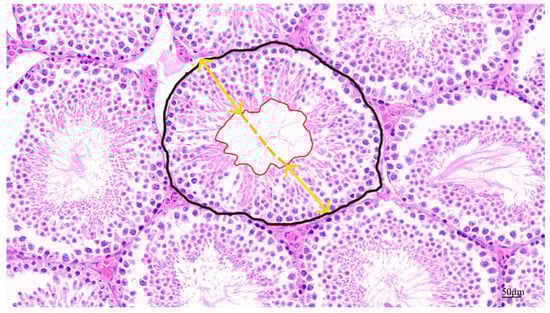

Fixed testicular tissue slides were stained with hematoxylin and eosin and photographed under light microscopy. Testicular tissue lumen area, seminiferous tubular area, epithelial height, and diameter were assessed. The black line area shown in Figure 2 indicates the cross-sectional area of the spermatogenic tubules and the red line area is the lumen area. The yellow line represents the vertical diameter of the varicocele, and the average length of the solid portion of the line represents the height of the varicocele epithelium [24]. Apoptosis in testicular paraffin sections was identified using a TUNEL staining kit (Servicebio, Wuhan, China) according to the instructions and the sections were analyzed using confocal fluorescence microscopy.

Figure 2.

Schematic diagram of parameters for quantitative assessment of testicular tissue in male mice.